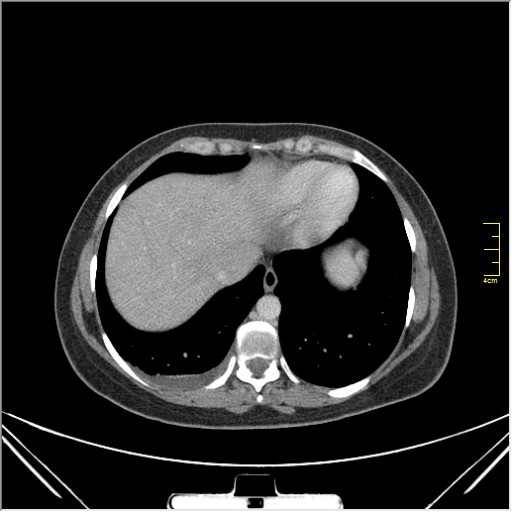

Женщина 32 года; месяц как кашляет. Повышения температутры тела не отмечала. Изначально выполнили рентгенографию. Что делать дальше?

Далее рекомендуем лабораторные исследования, КТ легких.

KT

Давайте определимся, для начала обозначим какие КТ признаки мы видим на представленных сканах. И главное это не перечисление вариантов диагнозов (если нет однозначного варианта); а определить что надо сделать следующим этапом для достижения окончательного диагноза.

Вполне адекватная тактика. КТ контроль через 3-4 недели после антибактериальной терапии, совершенно правильно.

В данном случае, пульмонолог решил пойти на бронхоскопию; был забор материала. Лабараторный анализ (ПЦР) выявил положительную реакцию на туберкулёз.